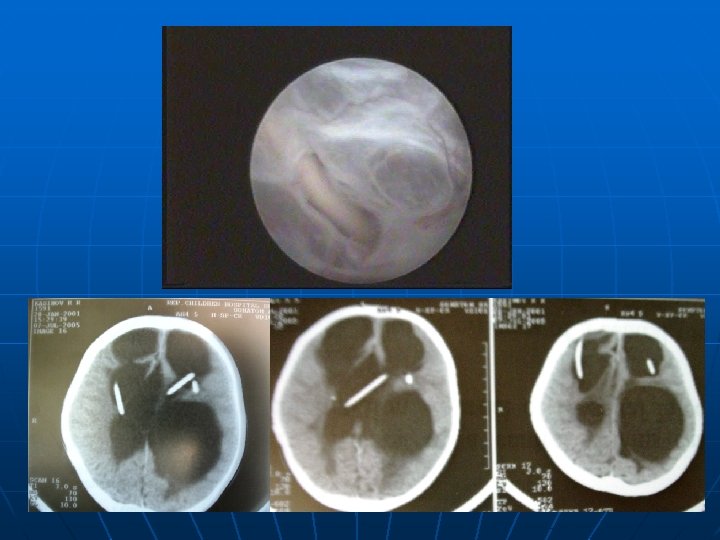

n n использование нейроэндоскопии при ревизиях ВПС, НЭС кистовентрикулостомии, ревизия вентрикулярного катетера с переустановкой, стентирования и фенестрации – все это приводит к более благоприятным условиям ликвородинамики.

Удаление мигрированного катетера при помощи эндоскопа